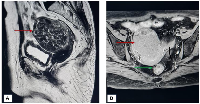

A 75-year-old, post-menopausal woman, presented to the gynecology outpatient department with a complaint of dull aching, moderate pain of insidious onset, localized in the lower abdomen from the last 9 months. There was no history of post-menopausal or post-coital bleeding. There was no history of loss of appetite or weight, or bowel and bladder disturbances. The patient had attained menopause 25 years back and was not on any hormone replacement therapy. Her obstetric history revealed that she had four pregnancies, all of which were conceived spontaneously. She was on medication for hypertension and diabetes for the last 16 years. She had undergone stenting for triple vessel coronary artery disease 6 years back. The patient was moderately built with a body mass index (BMI) of 29.6. General and other systemic examinations were unremarkable. Lab investigations, including serum lipid profile and thyroid profile, were within normal limits. Per-abdominal examination revealed a soft, abdominopelvic mass of 14 weeks gravid uterus, with restricted mobility. Upon speculum examination, the cervix was flushed with the vagina and the vaginal walls appeared atrophic and pale. On bimanual examination, the uterus was normal in size, and the same soft mass of approximately 8 × 8 cm was palpated. These findings were reconfirmed on rectal examination as well. Magnetic Resonance Imaging (MRI) of the abdomen was performed which revealed an intramural fibroid in the anterior wall, measuring 70 × 65 mm, and a smaller subserosal fibroid in the posterior uterine wall (Figure 1).

Figure 1

(A) T1 weighted (sagittal plane) image showing fibroid (red arrow) in the anterior uterine wall. (B) T2 weighted (transverse plane) image showing fibroid in the anterior uterine wall along with another subserosal fibroid (green arrow) arising from posterior wall.